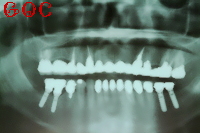

▼インプラント後![]() |

左右下顎奥歯を2本ずつの手術でしたが、手術は眠っている間に終わり、まったく痛みはありませんでした。